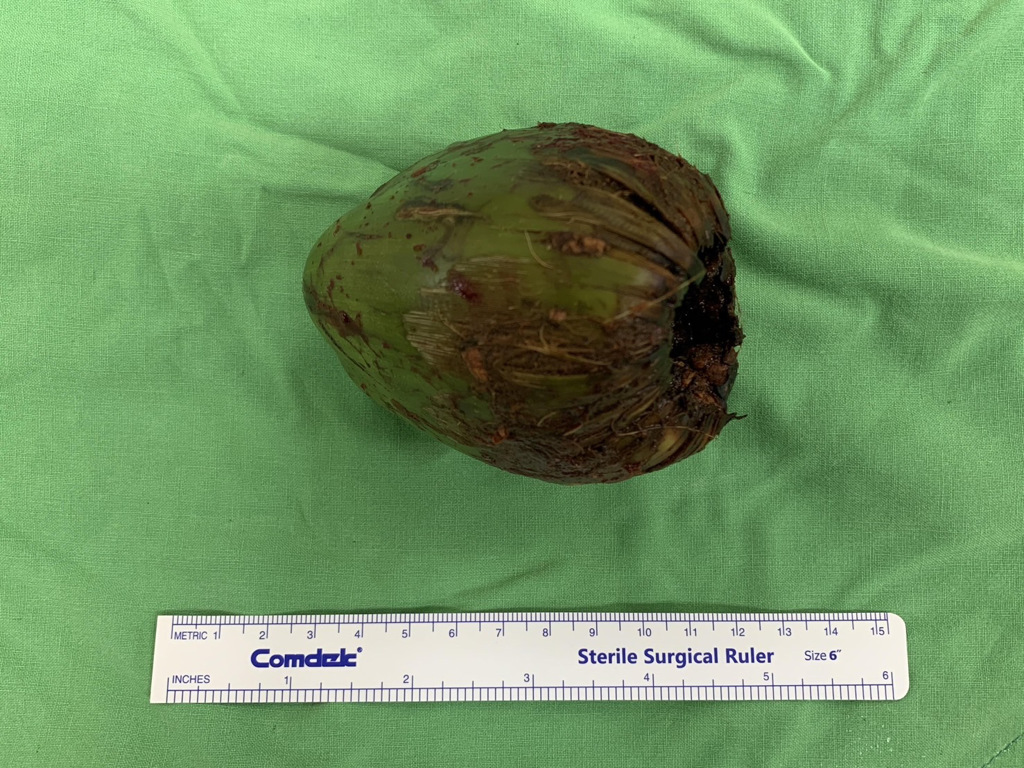

圖片來源 / 義大醫院一般醫學外科主任陳致一,下同

由於男子膀胱約有2000c.c.的尿液無法排出,膀胱腫得像顆橄欖球,再拖下去恐有膀胱破裂、直腸壞死的風險,因此院方緊急安排剖腹手術,最後從男子的直腸取出一顆直徑為7.5公分椰子。男子事後坦承是想尋求刺激才會塞進椰子,這起荒謬病例甚至登上《英國醫學期刊》,不過男子究竟是怎麼塞進這顆龐然大物,他並沒有透露。